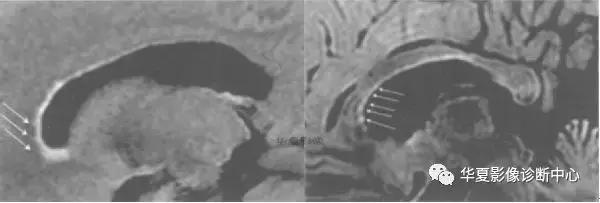

十二、铠甲征:MRI 增强后,大脑半球凸面硬脑膜,大脑镰及小脑幕弥漫性均匀性对称性强化,且广泛包绕脑组织形成“铠甲”样外观,称为“铠甲征”。

铠甲征多见于自发性低颅压综合征(SIH),这是一组由多种原因引起,以体位性头痛为典型临床表现的一组综合征,其侧卧位腰穿 CSF 压力<60 mmH2O。MRI 是诊断 SIH 的重要方法。SIH 患者头颅 MRI 常见的表现为: (1) 硬膜下积液或出血,厚度<1.0 cm,占位效应不明显; ( 2) 硬脑膜静脉窦扩张; (3) 脑结构移位,脑下沉; (4) 硬脑膜弥漫性增强,系SIH 早期、特征性 MRI 改变。MRM 常表现为在蛛网膜下腔 CSF 正常走行以外的团状、线状高信号影,这些高信号影与蛛网膜下腔相连,提示存在CSF 漏。

硬膜下积液被认为是颅内液体腔隙对 CSF 压力减低的一种代偿性反应。约 10%的患者出现硬膜下血肿。SIH 时 CSF 总量减少,由于脑组织容积相对恒定,因此颅内血容量代偿性增加,以硬脑膜和静脉窦为主的静脉系统明显扩张,同时由于脑组织移位,牵拉硬膜与蛛网膜之间的桥静脉或静脉窦使之破裂出血而引起继发蛛网膜下腔或硬膜下出血等表现。另外,低颅压经快速大量输液后易致已扩张渗血的静脉进一步破裂出血。窦汇扩张后下缘向外凸呈弧形改变。有报道此征象对低颅压综合征的特异性达94% ,此系由于硬脑膜静脉窦位于血-脑屏障之外,缺乏紧密的连接而产生代偿性扩张,毛细血管通透性增高,对比剂在硬脑膜微血管及间隙聚集。低颅压时易发生脑干结构移位,统称为“下沉脑”,影像学表现为部分病例双侧脑室缩小甚至呈缝隙状、基底池模糊、外侧裂变窄。鞍上池消失,视交叉下移,垂体受压。脑桥、间脑腹侧压向斜坡致桥前池狭窄或闭塞。中脑导水管开口位置下移。SIH 患者约 62% 出现小脑扁桃体下疝,一般为轻度。硬膜下积液、硬膜下血肿及脑结构移位,则预示存在较严重的 SIH。SIH致垂体增大可能是由于垂体周围组织为代偿 CSF 压降低而充血所致。这种表现可能会导致误诊断为垂体腺瘤或其他肿瘤。SIH 并发静脉窦血栓通常是继发于腰穿、硬膜外麻醉、鞘内注射药物等,其主要发生机制可能与 CSF 的有效容量降低使静脉瘀滞后再扩张而触发静脉窦血栓形成。SIH 好发于中年女性,多为急性或亚急性起病。平均年龄为 41.9 岁。SIH 主要应与肥厚性硬脑膜炎、脑膜癌病、化脓性、结核性脑膜炎等相鉴别。总之,SIH 的影像学特点为脑下沉及硬脑膜对称并均匀一致性增厚、增强,且形成包绕脑组织的“铠甲”样外观。